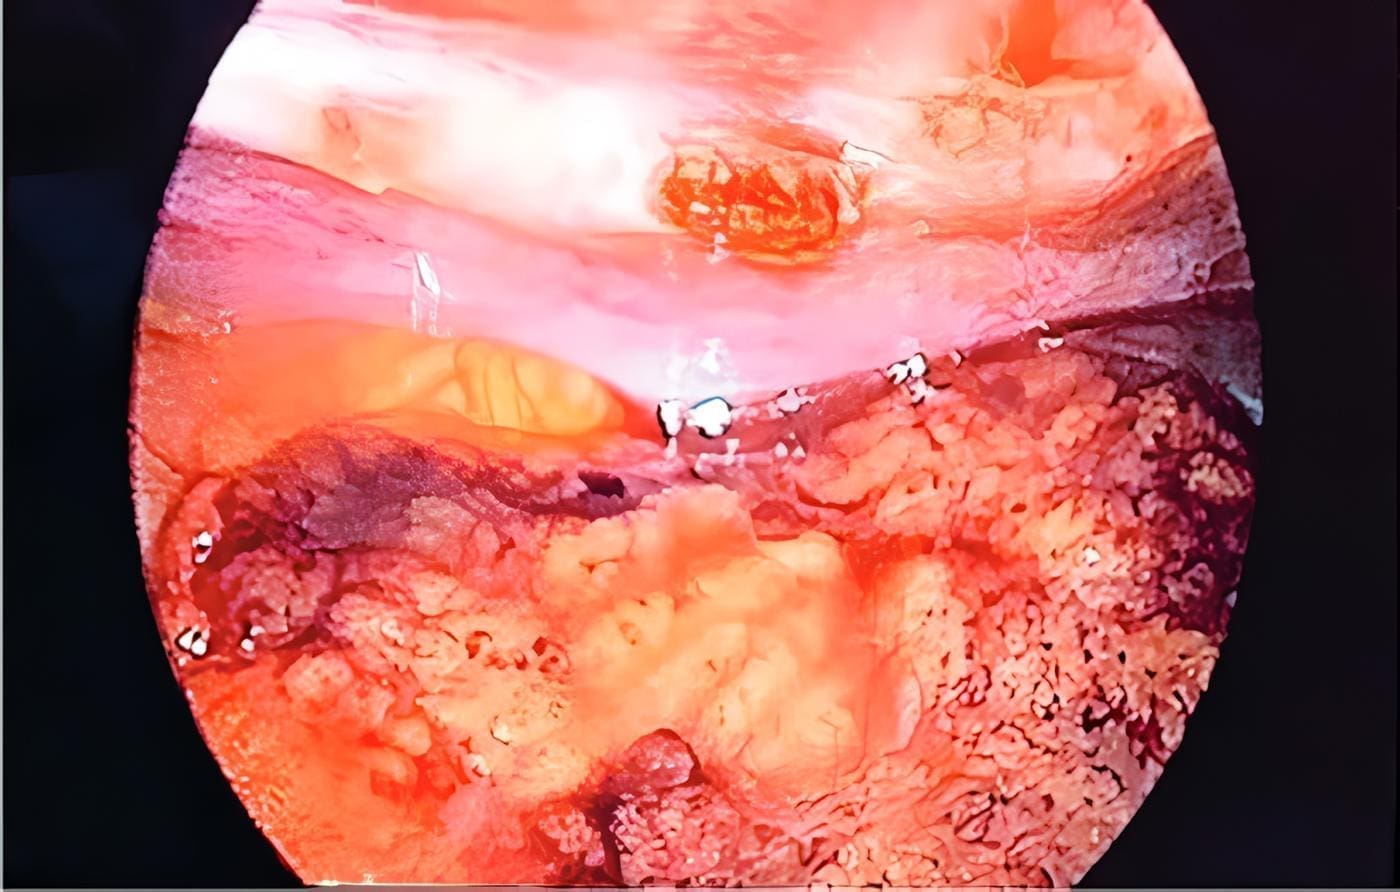

Figura 3. Hallazgo intraoperatorio en el que se observa el infarto del sector superior derecho del omento.

Fuente: fotografía tomada por los autores

Luego de 24 horas aumenta el dolor abdominal, por lo que se realiza laparoscopia exploradora. En el intraoperatorio, se confirma necrosis del sector superior derecho del epiplón mayor; se realiza la resección con ligasure® (figura 3).